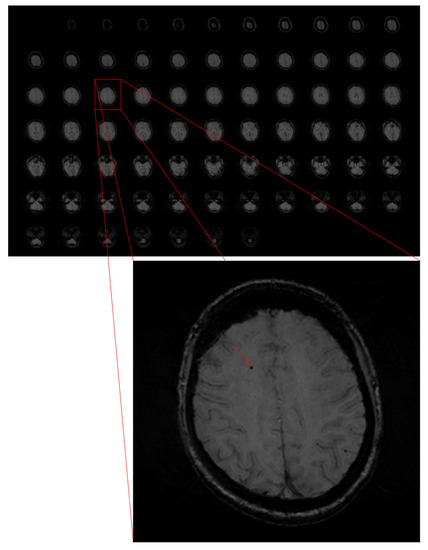

In the case of automatic detection systems, it is fairly easy to mistake microbleeds with other objects, mainly because of their small size compared to the whole image, their similarity to the background, and lesion mimics (see Figure 1). For instance, an oval cross-section through a vessel or calcification is very similar to a CMB. The differences between microbleeds and other objects can be observed when rating the whole MRI altogether.

Figure 1. Sample of SWI sequence from MR image. One of the slices is enlarged to visualise a cerebral microbleed, marked with the red arrow.

In our research, we decided to enlarge our images. There were two main reasons. The first one was the size of CMB. As it is presented in the Figure 1, they are really small objects. Resizing the image to make it bigger also makes objects more visible. In this case, there are not many images, so a slight extension of training time is acceptable.